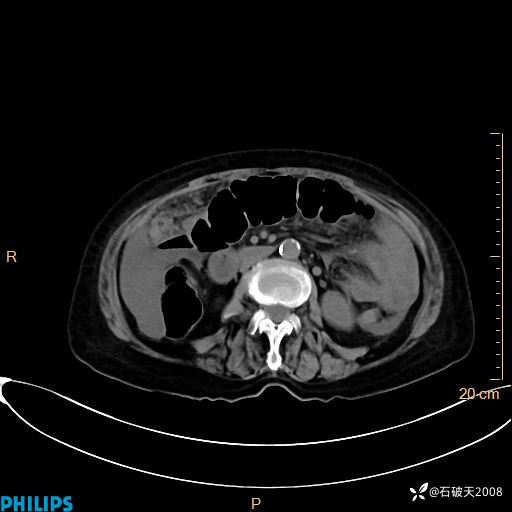

静脉期